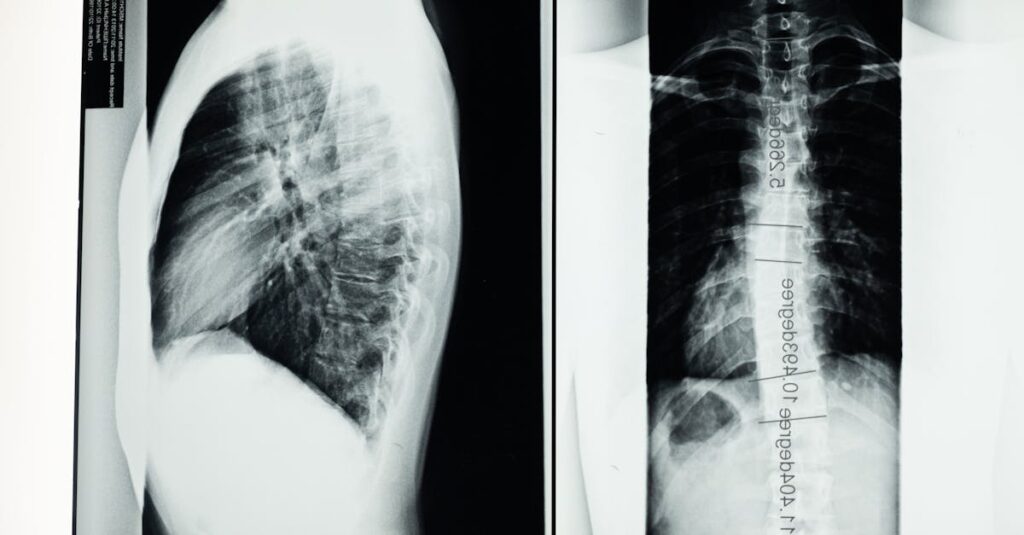

Quels examens sont nécessaires avant de commencer un traitement de décompression?

Une IRM ou une radiographie est généralement nécessaire pour évaluer l’état de la colonne vertébrale.

Quels examens permettent de diagnostiquer une hernie discale?

Une IRM ou une radiographie est utilisée pour confirmer le diagnostic d’une hernie discale.